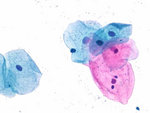

Los kits de tinción Cytocolor® son la elección óptima para las investigaciones ginecológicas. Proporcionan información valiosa relativa a la integridad, el estado hormonal y la flora vaginal en frótis ginecológicos. Los kits no sólo son cómodos, sino también rápidos, permitiéndole producir tinciones en tan sólo tres minutos. En contraste con las tinciones de Papanicolaou clásicas, Cytocolor® no requiere tinción naranja. Así pues, tanto las células maduras como las queratinizadas aparecen de color rosa en vez de naranja.

Los kits de tinción Cytocolor® son la elección óptima para las investigaciones ginecológicas. Proporcionan información valiosa relativa a la integridad, el estado hormonal y la flora vaginal en frótis ginecológicos. Los kits no sólo son cómodos, sino también rápidos, permitiéndole producir tinciones en tan sólo tres minutos. En contraste con las tinciones de Papanicolaou clásicas, Cytocolor® no requiere tinción naranja. Así pues, tanto las células maduras como las queratinizadas aparecen de color rosa en vez de naranja.